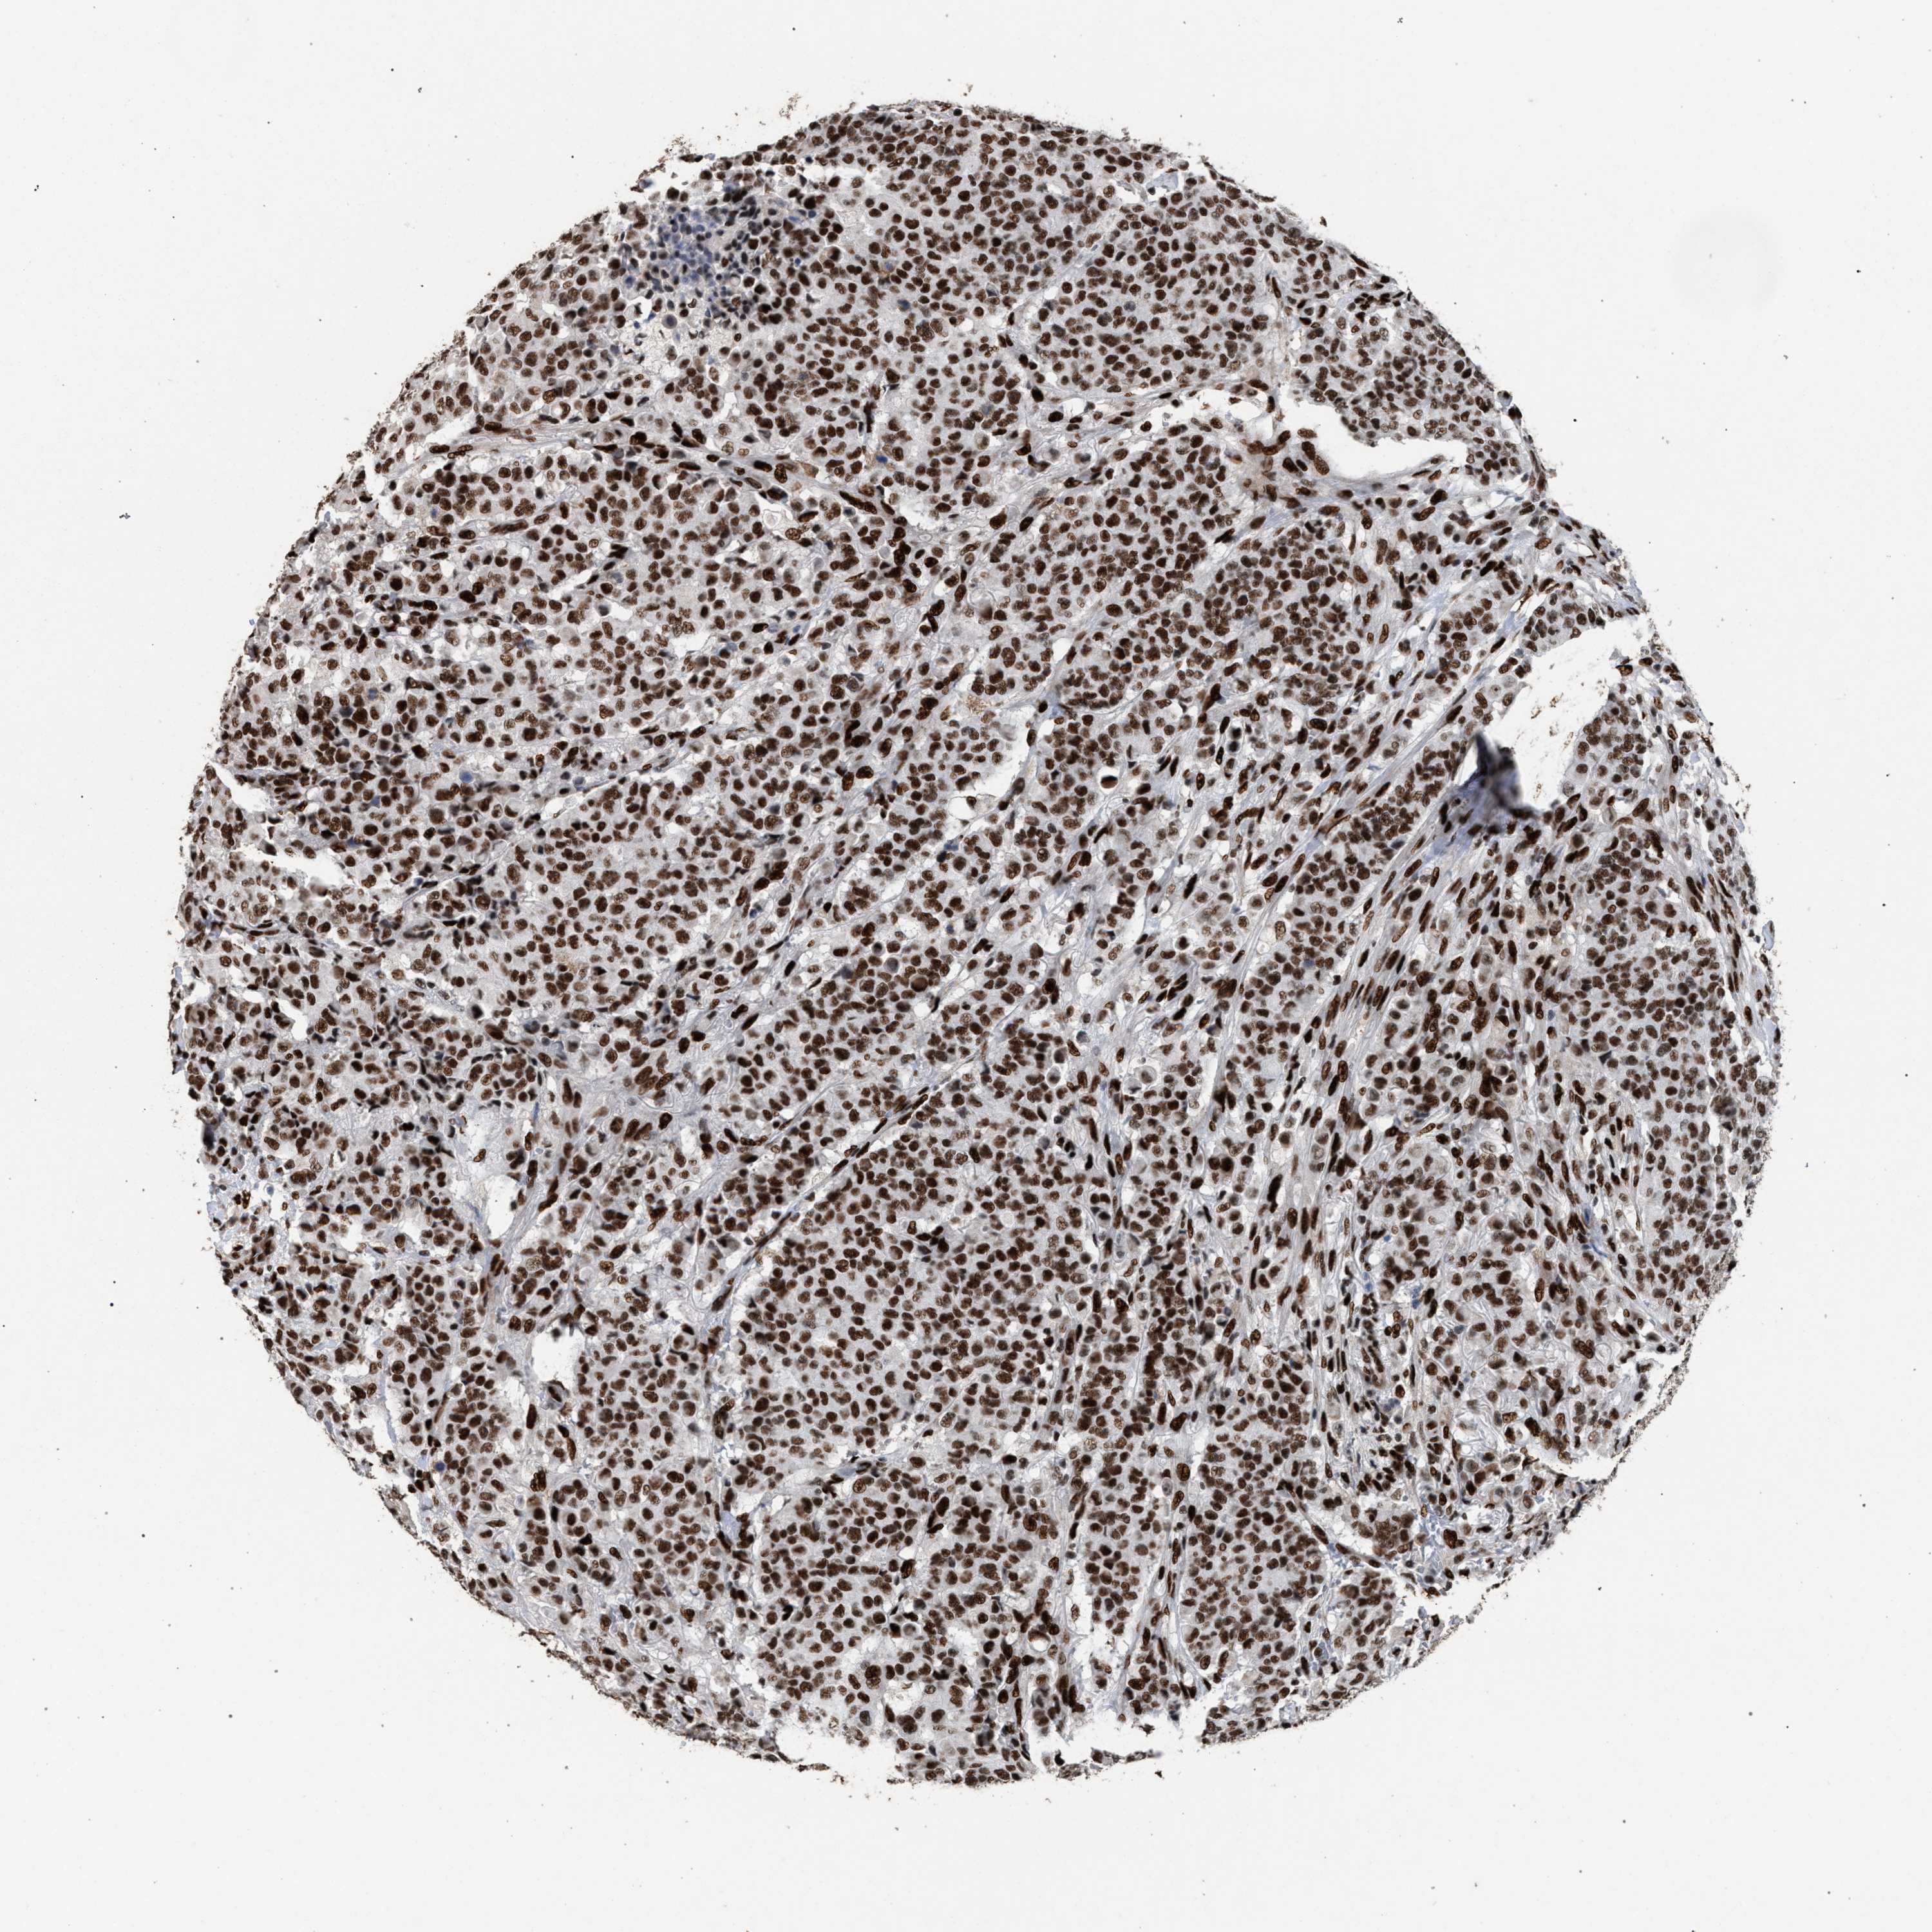

CANCER BREAST CANCER Show tissue menu

BRCA TCGA BRCA VALIDATION PROTEIN EXPRESSION